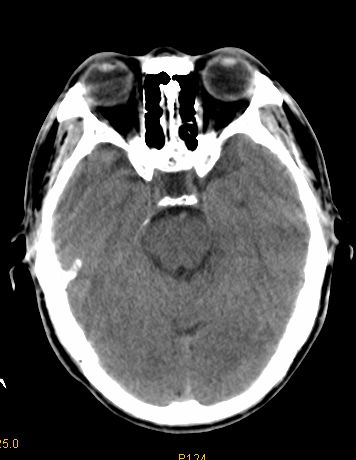

男 42岁 头痛20天

左顶叶见片状低密度影,边界不清,内见斑片状等密度影。考虑转移性肿瘤可能性大,建议ct增强或mr增强扫描。建议胸部检查,排除肺部病变。

左顶叶见片状低密度影,内似见结节状略高密度影,建议增强扫描。

胸部ct未见异常。

左顶叶见片状低密度影,边界不清,内见斑片状等密度影。考虑转移性肿瘤可能性大,建议ct增强或mr增强扫描。建议胸部检查,排除肺部周围型腺癌。